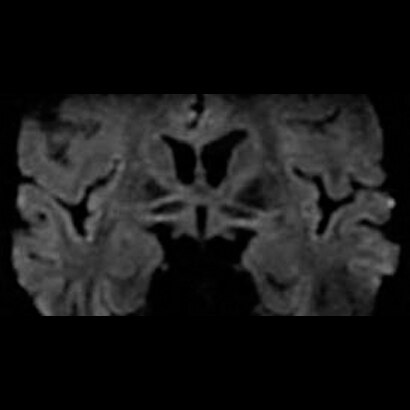

With SilentSuite, which is both revolutionary and proprietary, the SIGNA Pioneer reduces dB levels from an ear-splitting, motorcycle-level 91dB to within 3dB of scan room ambient noise. Along with this dramatic advance comes the first-ever complete Silent Neuro Exam that includes Diffusion Weighted Imaging (DWI).